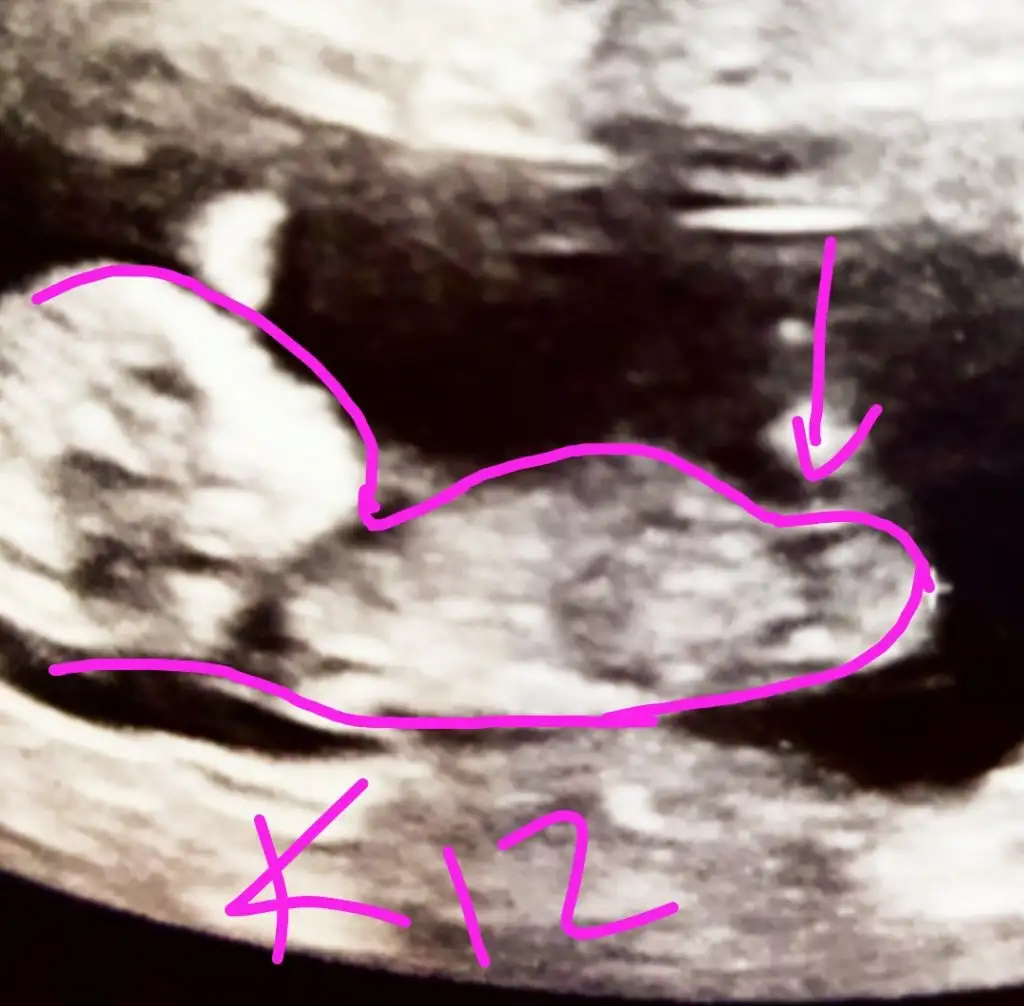

Erkek görünüyor kesede karindansa kız vajinal ise erkek diğer USG kaç haftalık en iyi 11 12 13 haftalar olmalıMerhaba ikra meyra arkadaşımın bebişine de bakarmısın kese ve nubunaEki Görüntüle 2753467 Eki Görüntüle 2753468 Eki Görüntüle 2753470

Erkek gibi sanki eminde olamadımUsg net değil şimdi net bı bakar mısın Eki Görüntüle 2753582 Eki Görüntüle 2753583 Eki Görüntüle 2753585

Geçen arkadasin ki işaretle göstermişti benimki de gösterir misinErkek gibi sanki eminde olamadım

Kese karından usg 12 haftalıkErkek görünüyor kesede karindansa kız vajinal ise erkek diğer USG kaç haftalık en iyi 11 12 13 haftalar olmalı

Evet nuba göre erkek görünüyorNuba göre erkek mi diyorsunuz

Emin olamadım yüz üstü gördüğüm nubmu bilemedim ama renkle oynadim .ama 14+ görünüyor yanitabilir haftası beniGeçen arkadasin ki işaretle göstermişti benimki de gösterir misin

TeşekkürlerEmin olamadım yüz üstü gördüğüm nubmu bilemedim ama renkle oynadim .ama 14+ görünüyor yanitabilir haftası beni